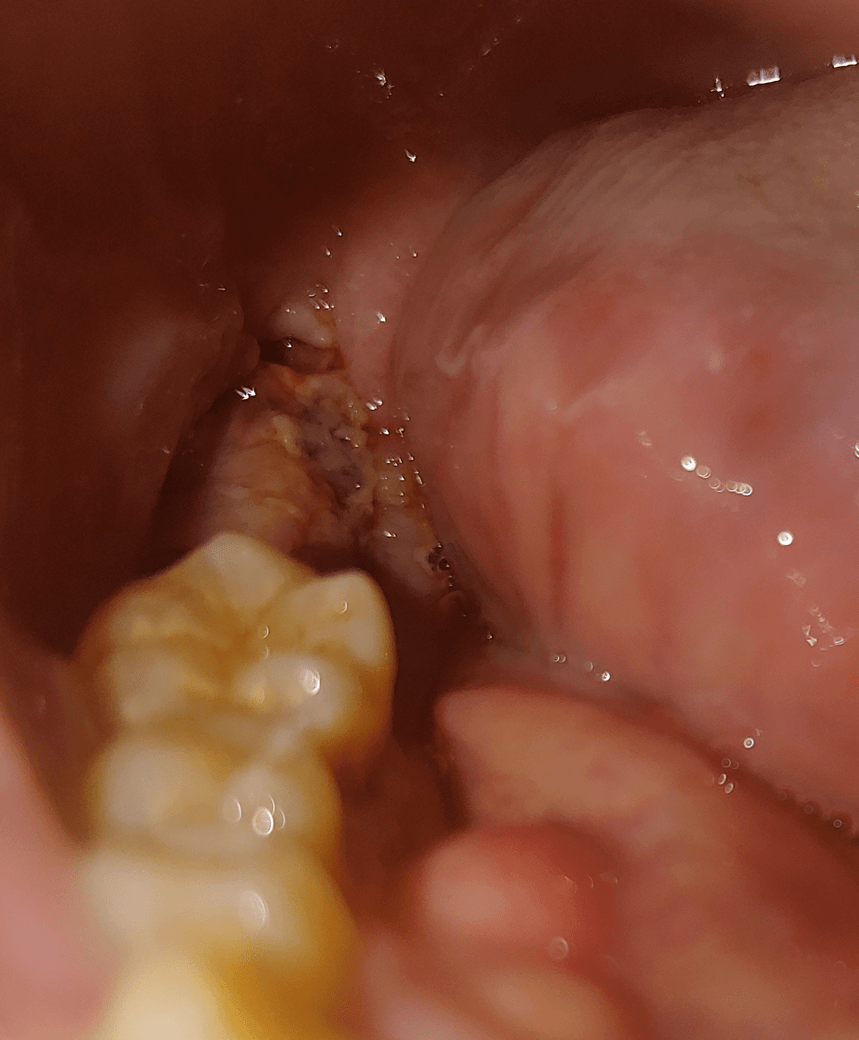

이거 드라이소켓 인지 확인 좀 해주에요ㅜ

매복 사랑니와 사랑니 바로 옆에 붙어 있던 어금니 이렇게 두개를 3월17일 오후4시에 발치 했습니다.

사진 보시면 어제까지는 검은색으로 덮혀있었는데 그냥 확인한번 해봤는데 흰색이 돼있네요?

드라이소켓 초기 증상인가요??

• 1번 째 사진

아직까지는 크게 드라이소켓을 의심할만한 병변으로 보이지 않습니다.